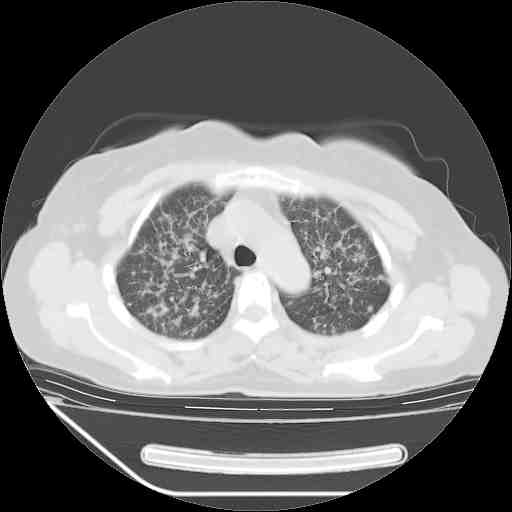

下面是今天刚刚做的,在上海治疗,吃了家属也说不清的一种药,一个月1万左右,

考虑  腺癌肺内转移,治疗较前病灶缩小、减少

肺癌并肺内转移,这种疾病治疗后在影像上看略有好转,不是很显著,但是肿瘤治疗效果影像只是一方面。

支持肺癌并肺内淋巴管炎,  原发灶小了,但转移较前片明显了.

支持右肺下叶周围型肺癌并肺内淋巴管炎,  原发灶小了,但转移较前片明显了.。

标准的细支气管肺泡癌呀!治疗后病情有所控制,也没治愈的迹象!

标准的癌性淋巴管炎!!距大去之日不远已.

应该是比较典型的细支气管炎,4个月的时间不说明问题;有时候疾病是有个相对稳定期的,如果喝10元一斤的茶叶估计也会这样。